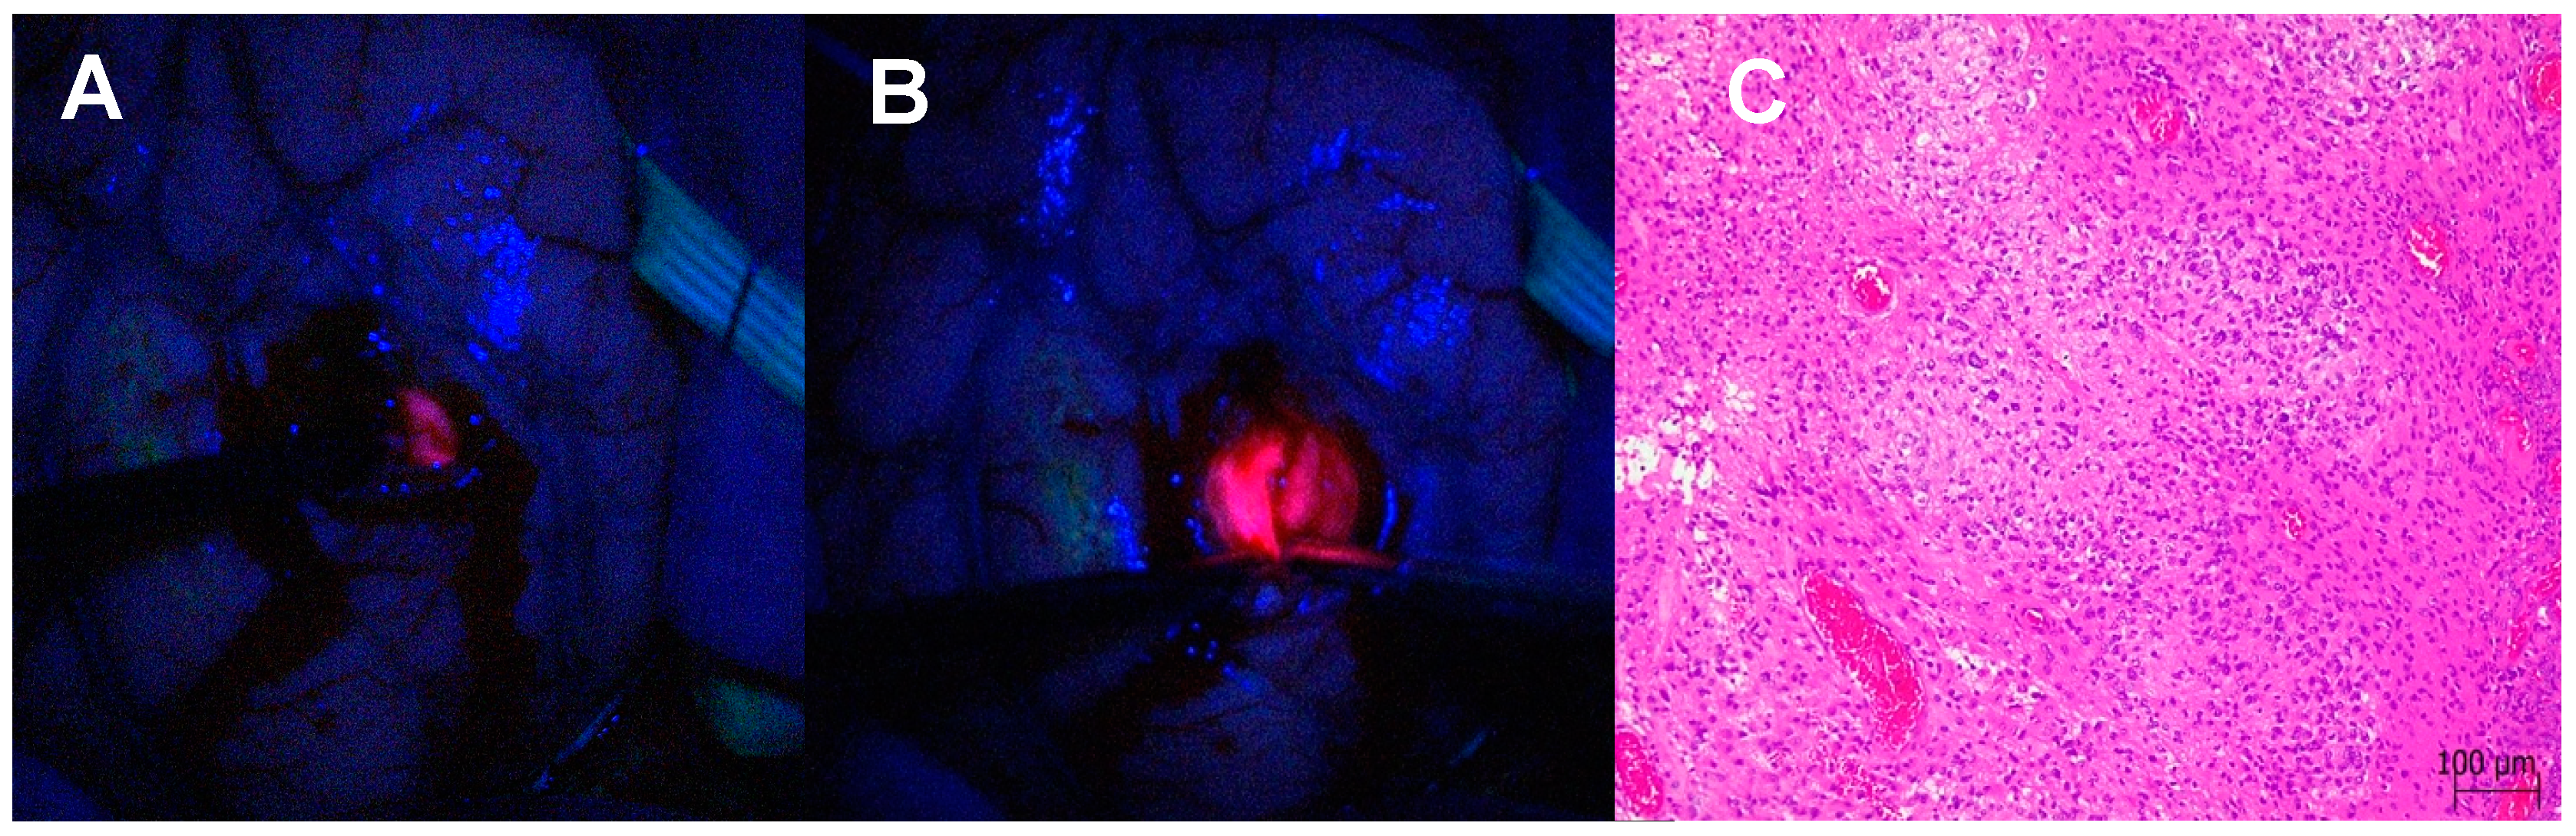

3.1.3. Satellite Foci Identification and Resection